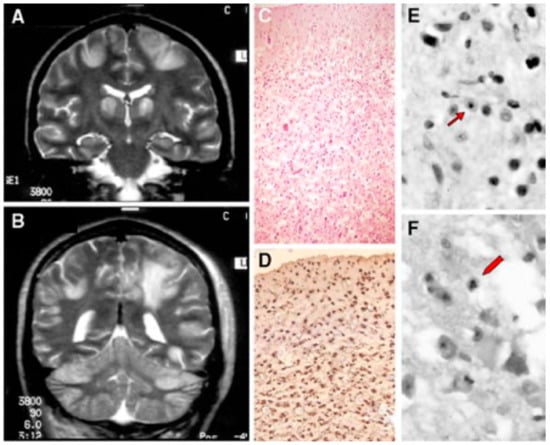

- Simonati, A.; Filosto, M.; Savio, C.; Tomelleri, G.; Tonin, P.; Dalla Bernardina, B.; Rizzuto, N. Features of Cell Death in Brain and Liver, the Target Tissues of Progressive Neuronal Degeneration of Childhood with Liver Disease (Alpers-Huttenlocher Disease). Acta Neuropathol. 2003, 106, 57–65. [Google Scholar] [CrossRef] [PubMed]

- Filosto, M.; Tomelleri, G.; Tonin, P.; Scarpelli, M.; Vattemi, G.; Rizzuto, N.; Padovani, A.; Simonati, A. Neuropathology of Mitochondrial Diseases. Biosci. Rep. 2007, 27, 23–30. [Google Scholar] [CrossRef]